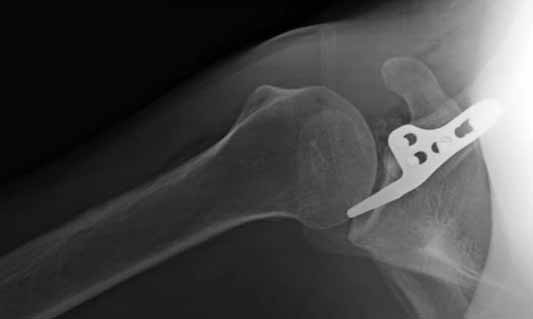

foto

2.JPG

Замечание понял, спасибо и нормальные рентгенограммы, молодец!

Во вторых, это хорошо что нашли длинную пластину, я об этом писал "пластина короткая, не покрывает медиальный диафизарный фрагмент ключицы", и у нас не получилось, пластина не выдержала...

На конференции EFORT в Копенгагене поднимался вопрос о пластинах для остеосинтеза ключицы с крючком. Не имею возможность осветить все что там услышал. Но у меня появилось понимание о импиджмент синдроме, о необходимой длине крючка, о правильном позиционировании пластины, о лизисе акромиона и т.д.

Мне кажется что если понять принципы, то можно использовать и короткую пластину. Что мы с успехом применяли раньше и применяем сейчас, но уже более осознанно. В вашем случае Серж, у меня стойкое ощущение, что необходима дополнительная иммобилизация, так как неправильно выбрано место введения крючка и при ранней нагрузке пластину просто вырвет. Если вам несложно не могли бы вы продемонстрировать прямую и боковую проекцию и в более хорошем качестве. ИМХО

На чем у Вас обосновано" стойкое ощущение, что необходима дополнительная иммобилизация, так как неправильно выбрано место введения крючка"?

Теоретически можно использовать и короткую пластину. Но на операции дистальный отломок( акромиальный конец ключицы ) был коротким и оскольчатым, поэтому крючок и использование там блокированных винтов в пластине было очень уместно. Доступ - "сабельный удар". Точка введения крючка - сразу сзади от ключично-акромиального сустава. Если честно - больше внимания уделяли репозиции отломков и адекватному расположению пластины на ключице :-) крючок проверяли на прочность фиксации за акромион и полный объем движений в плечевом суставе. После операции рука на косынке, нагрузку ограничили. Снимки есть в нормальном разрешении, но здесь "размер файла не превышал 75 кб." Если есть необходимость залью в пикассу...